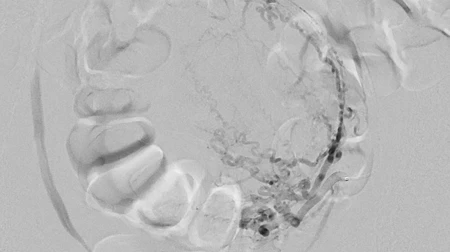

Uterusmyomembolisation